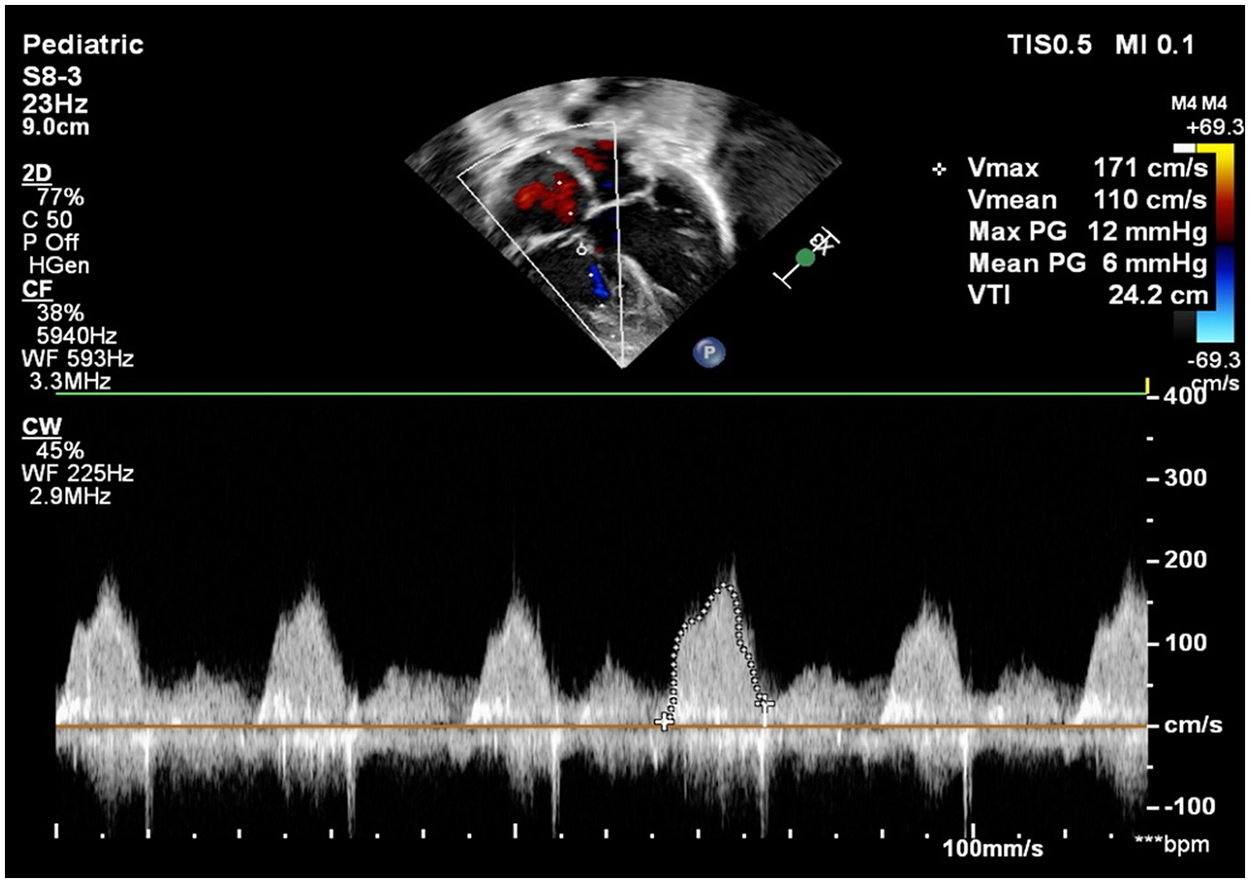

Parachute Tricuspid Valve in Association with Cyanotic Congenital Heart Disease and Juxtaposed Atrial Appendages in a 1-Year-Old Male: A Rare Anatomical Association

Abstract Parachute tricuspid valve (PTV) is an exceedingly rare congenital anomaly, often found in association with acyanotic heart defects. Its occurrence in association with cyanotic congenital heart disease (CCHD) is even less common. We report the case of a 1-year-old male presenting with complex cyanotic heart disease along with parachute tricuspid valve. Detailed evaluation revealed a constellation of anomalies, including parachute tricuspid valve in association with double outlet right ventricle (DORV) with D-malposed great arteries, severe pulmonary stenosis, and a non-routable ventricular septal defect. Echocardiography played a vital role in defining the complex anatomy and guided the decision toward single-ventricle palliation. This case underscores the importance of meticulous anatomical assessment in patients with congenital heart disease and adds to the sparse literature on this rare condition.

Cyanotic congenital heart disease, Double Outlet Right Ventricle, Parachute tricuspid valve, Pulmonary stenosis, Ventricular septal defect